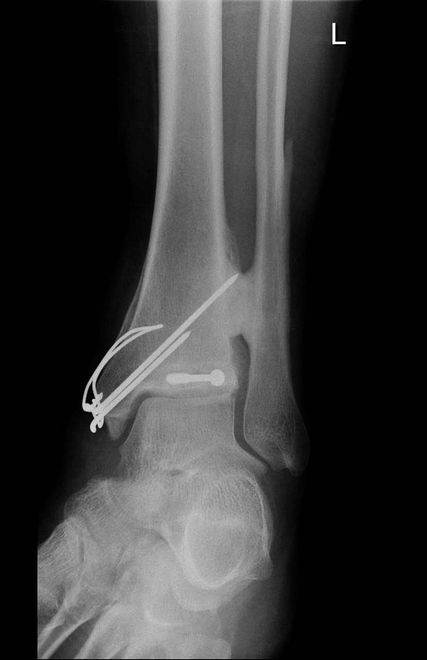

Abb. 1: Erstdiagnose: undislozierte Innenknöchelfraktur. Intraoperativ: instabile Maisonneuve-Verletzung (= Innenknöchelfraktur + proximale Fibulafraktur), rupturiertes eingeschlagenes AITFL, Naht AITFL nach Stellschraubeneinbringung, Innenknöchel-Verschraubung